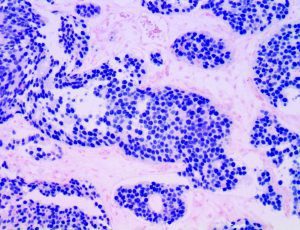

It is the ICU physician who is most likely to witness one of the deadliest manifestations of the abnormal immunological response, the cytokine storm syndrome (CSS). This response is also referred to by some as the cytokine release syndrome (CRS). CSS is characterized by continuous activation and expansion of macrophage and lymphocyte populations, which secrete large amounts of cytokines, causing the cytokine storm. This massive cytokine release is akin to hemophagocytic lymphohistiocytosis (HLH) disease, a syndrome characterized by initial unchecked and persistent activation of cytotoxic T lymphocytes and NK cells.

Clinical and laboratory manifestations of HLH include fever, enlarged liver and/or spleen, neurologic dysfunction, coagulopathy, liver dysfunction, cytopenias (i.e., low levels of erythrocytes, leukocytes, and/or platelets), hypertriglyceridemia, hyperferritinemia, hemophagocytosis, and eventually diminished NK cell activity as the immune system becomes progressively paralyzed. HLH can be familial (primary HLH) or secondary to another disease process (sHLH), such as rheumatic disease, in which it is referred to as macrophage activation syndrome (MAS, characterized by elevated ferritin).